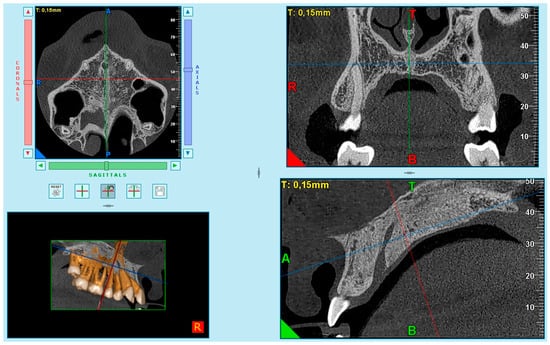

Based on the difficulties presented in some samples in obtaining complete visualization of the midpalatal suture in a single cut, it was decided to divide the maxilla into two cuts: the anterior region (palatine processes of the maxillary bone) (Figure 1) and the posterior region (palatine bone) (Figure 2). This small modification to Angelieri et al.’s method [40] allowed us to better standardize the systematic and meticulous observation of the suture.

The images were obtained as follows. First, in the multiplanar reconstruction screen, the skull image was manipulated so that the vertical and horizontal lines were overlaying the MPS in the axial and frontal cuts.

Afterward, in the sagittal view, the patient’s head was adjusted so that the horizontal reference line coincided with the median region of the palate, which is the cancellous bone between the upper and lower cortical bones.

After that, the final image was used in the axial plane, for evaluation and classification of the skeletal maturation stage of the MPS according to the method of Angelieri et al. [39].

Figure 2. Posterior axial section—palatine processes of the maxillary bone.